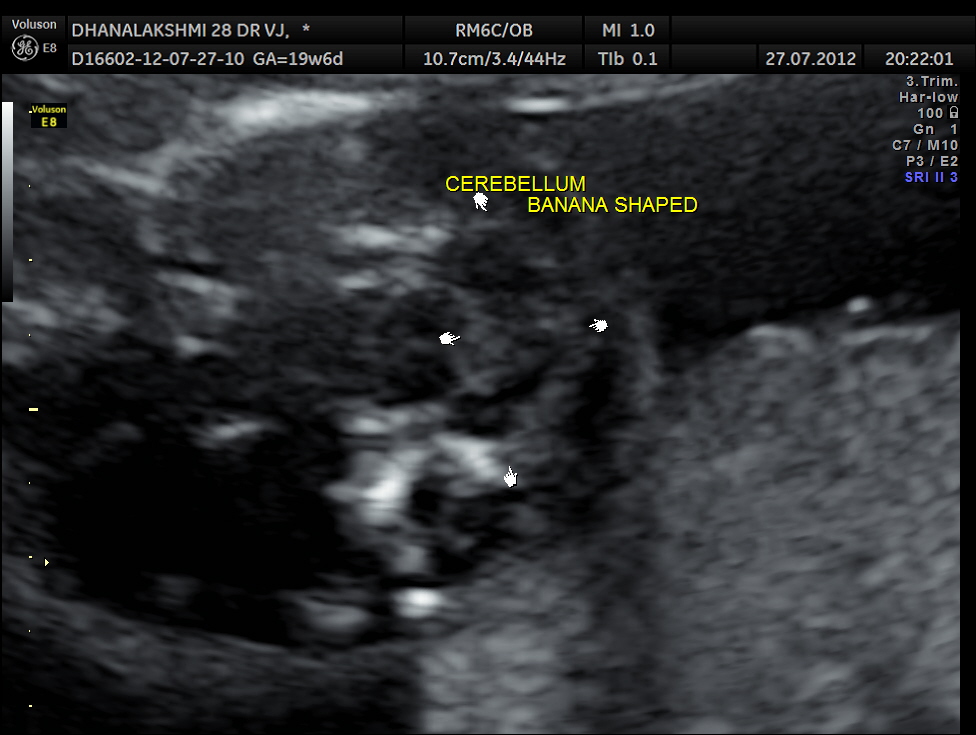

The following was the picture of the head showing the ” lemon sign”of the skull and the” banana sign “of the cerebellum.